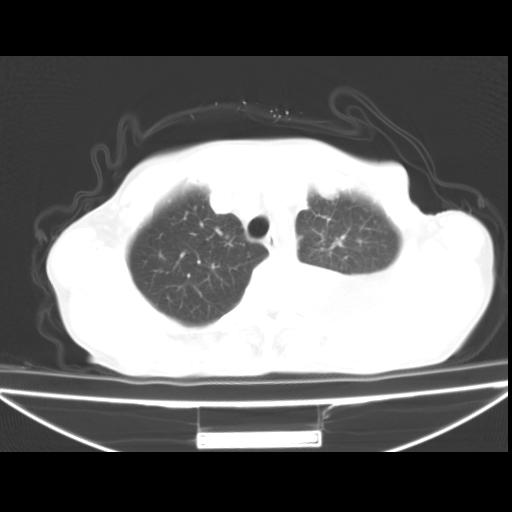

以下是引用随光逐影在2010-3-24 19:15:00的发言:[br]结合病史,考虑双肺及纵隔淋巴结多发转移、左侧胸膜转移并左侧大量胸水,左下肺膨胀不全。

以下是引用zxl51642在2010-3-24 18:49:00的发言:[br]结合乳腺癌术后病史,考虑双肺及纵隔淋巴结多发转移、左侧胸膜转移并左侧大量胸水、左下肺膨胀不全。